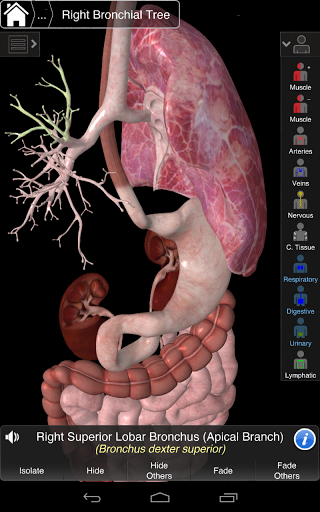

Основна анатомія 3 - це найновіша технологія та новаторський дизайн. Ріжучий 3D-графічний движок, зроблений на замовлення 3D4Medical з усього світу, наділений високоінформативною анатомічною моделлю і забезпечує високу якість графіки, яку не може досягти ніхто інший конкурент.

Програма являє собою унікальний підхід до вивчення загальної анатомії. Графіка не має аналогів і навчається, використовуючи інформативний контент та інноваційні функції, багатий та захоплюючий досвід.

НОВІ 3D-ТЕХНОЛОГІЇ

Основна Анатомія 3 чутлива, візуально приголомшлива і легка. Додаток повністю 3D, що означає, що ви можете переглядати будь-яку анатомічну структуру окремо, а також з будь-якого кута.

---- Більше 4000 дуже детальних анатомічних структур

---- Латинська номенклатура для кожної анатомічної структури